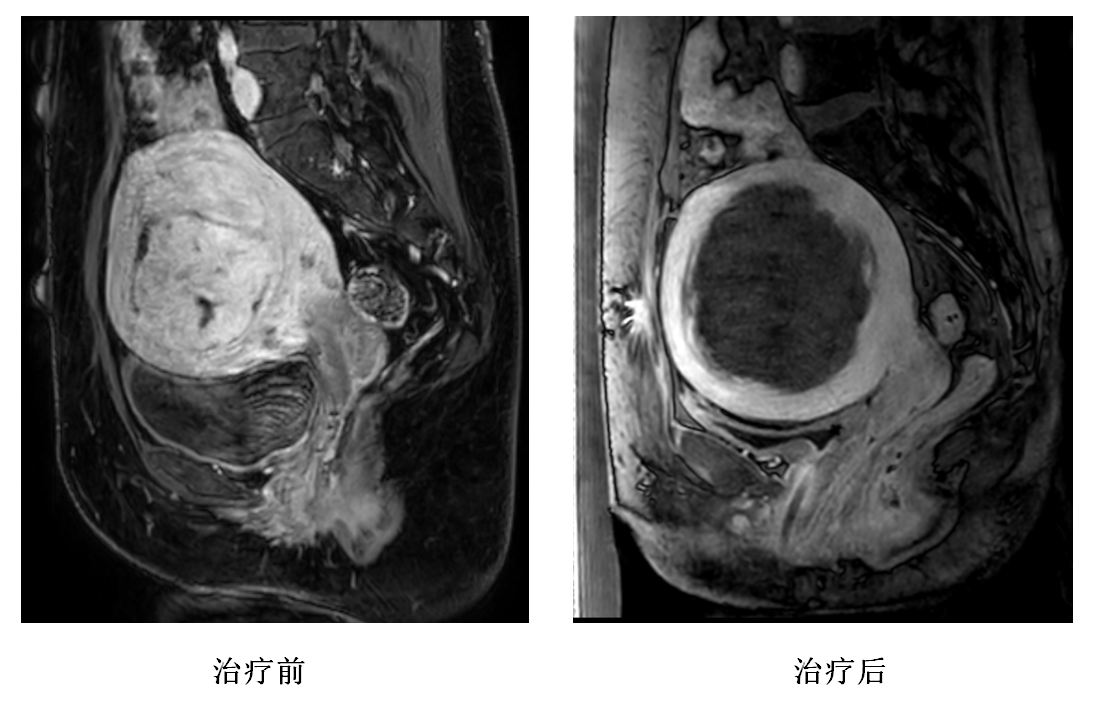

日前,患者龙女士的子宫肌瘤病灶被磁波刀(磁共振引导下高强度精确聚焦超声热消融术)成功消融,术后病灶无灌注区状态,成功地保住子宫功能的同时,还免除遭受传统手术创伤的疼痛。

龙女士受子宫肌瘤病症困扰已久,辗转多家医院治疗效果不佳,于2024年2月24日到海南医院就诊。磁共振检查结果显示,其子宫肌瘤已“野蛮”成长至填满整个子宫内壁,基本上剥夺了患者的子宫功能。海南医院放射诊断科主任陈志晔充分了解龙女士病情,从她的诉求出发,为其制定了一个两全方案,既能保住子宫功能又无创无痛的磁波刀治疗方案。

治疗时间共持续了4小时。术后检查显示患者病灶呈无灌注区状态,表明手术治疗效果显著。陈志晔说,相较于传统手术切除,海南医院这种治疗方法无需开刀,减小手术风险,术区创伤小,缩短患者恢复时间,更重要的是可保留患者子宫功能。